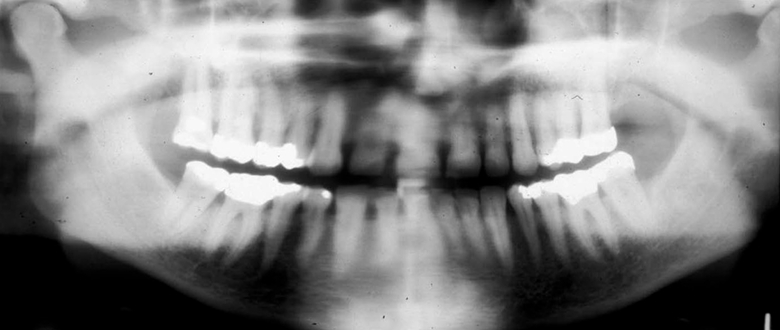

What is wrong with this image?

A

too far back

Q

What happens if a panoramic is taken too far back?

• Anterior teeth widened and blurred.

• Inferior turbinates and meati spread across maxillary sinuses.

• Condyles close to or cut off side of image.